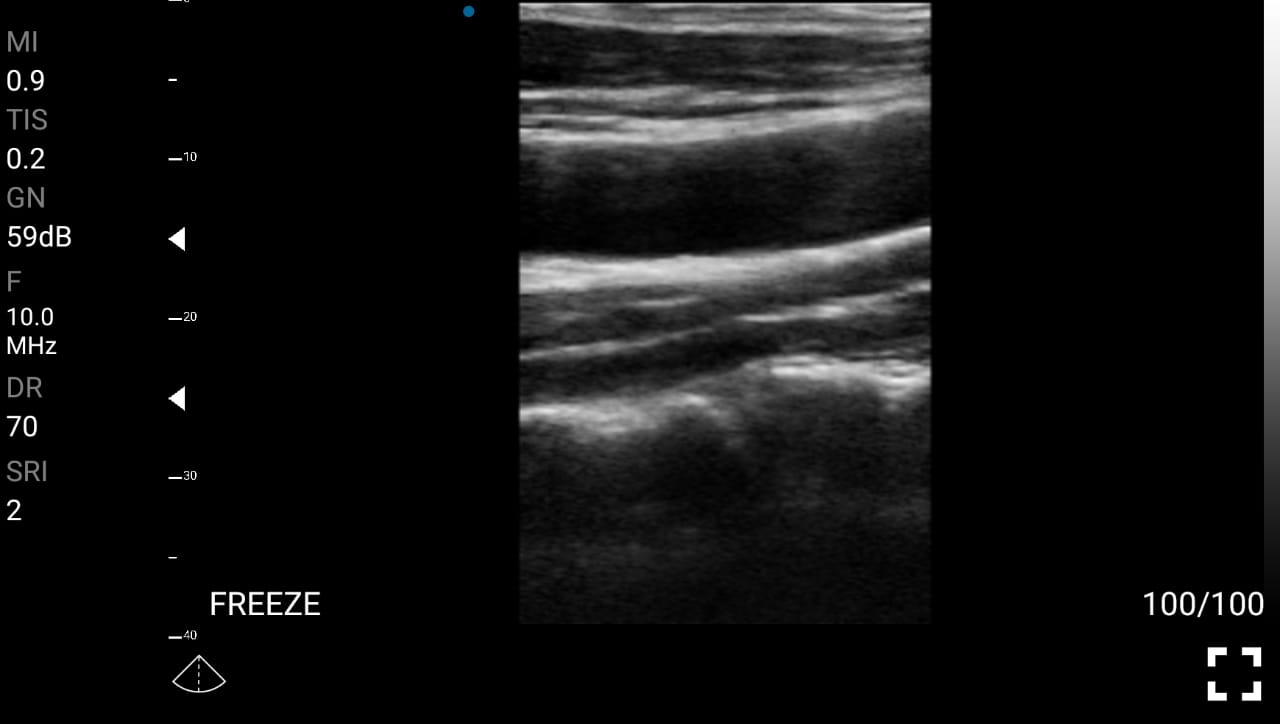

Παραδείγματα

Ολες οι παραπάνω απεικονιστικές εξετάσεις έχουν ληφθεί από φορητή συσκευή όπως: Apple Iphone, Tablet, Samsung Mobile Phones και διάφορες άλλες φορητές συσκευές.